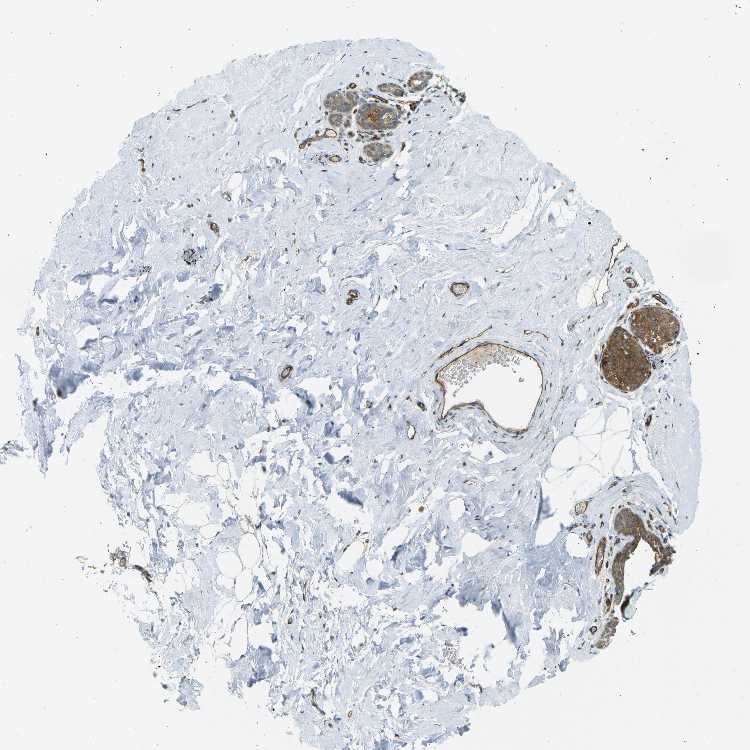

BREAST - Antibody stainingi

Antibody staining in the annotated cell types in the current human tissue is reported as not detected, low, medium, or high, based on conventional immunohistochemistry profiling in selected tissues. This score is based on the combination of the staining intensity and fraction of stained cells.

Each image is clickable and will lead to virtual microscopy that enables deeper exploration of all samples and also displays staining intensity scores, fraction scores and subcellular localization as well as patient and tissue information for each sample.

Antibody CAB010104

Adipocytes Not detected

Glandular cells Medium

Myoepithelial cells Medium